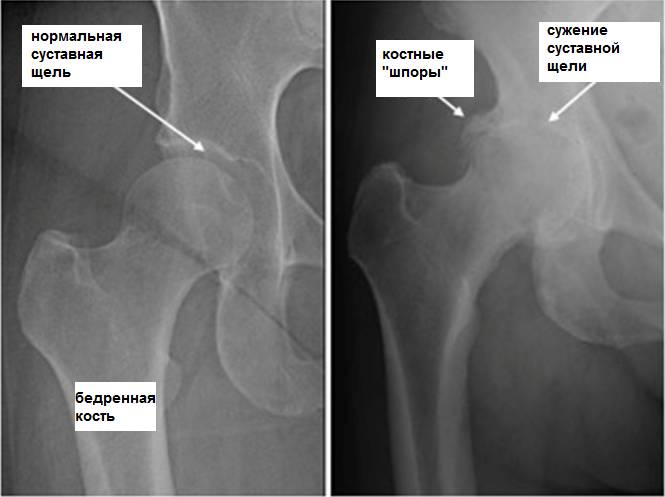

Деформирующий остеоартроз представляет собой более сложное состояние, при котором болит тазобедренный сустав во время беременности. Женщина испытывает не только боль, но и ограничение движений, особенно при отведении и приведении ноги. Боль может проявляться как при ходьбе, так и в состоянии покоя.

Хронические заболевания

Если у женщины до беременности были скрытые заболевания костной системы, то в период вынашивания ребенка они могут проявиться с удвоенной силой, особенно это касается тазовых костей. Боль в тазобедренных суставах во время беременности может возникать по следующим причинам:

- дисплазия тазобедренных суставов;

- остеоартроз тазобедренных суставов.